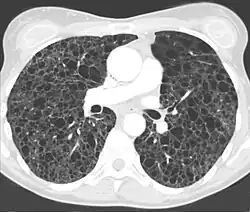

Die eindeutige Diagnose ist mittels Computertomographie oder durch eine Lungenbiopsie möglich. Der CT-radiologische Befund[7] ist typisch und erlaubt in aller Regel die Diagnosestellung.

- ↑ Abbildung aus RadioGraphics ( des vom 27. September 2007 im Internet Archive) Info: Der Archivlink wurde automatisch eingesetzt und noch nicht geprüft. Bitte prüfe Original- und Archivlink gemäß Anleitung und entferne dann diesen Hinweis.

- ↑ G. F. Abbott, M. L. Rosado-de-Christenson, A. A. Frazier, T. J. Franks, R. D. Pugatch, J. R. Galvin: From the Archives of the AFIP: Lymphangioleiomyomatosis: Radiologic-Pathologic Correlation. In: Radiographics. 25, 2005, S. 803–828, doi:10.1148/rg.253055006.